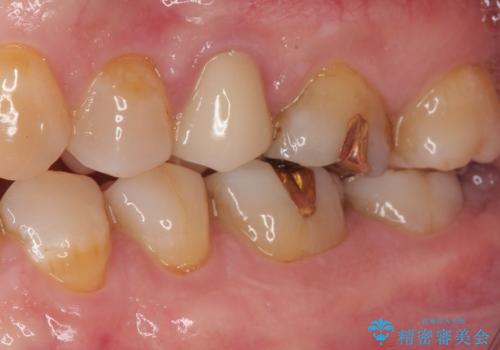

精密検査を行ったところ、上顎左側第二小臼歯のインレー(詰め物)が欠け、その内部に虫歯が進行している状態でした。幸いにも虫歯は神経まで達しておらず、神経を残した治療が可能と判断しました。

まず、虫歯を丁寧に除去。

欠損範囲が大きかったため、オールセラミッククラウンによる補綴治療を行いました。

「他の歯も、せっかくなら精度の良いものに替えておきたい」とのご希望があり、

上顎左側第一大臼歯

下顎左側第一大臼歯

に入っていた保険診療の銀歯(メタルインレー)を、精度の良いゴールドインレーへやり替えを行いました。